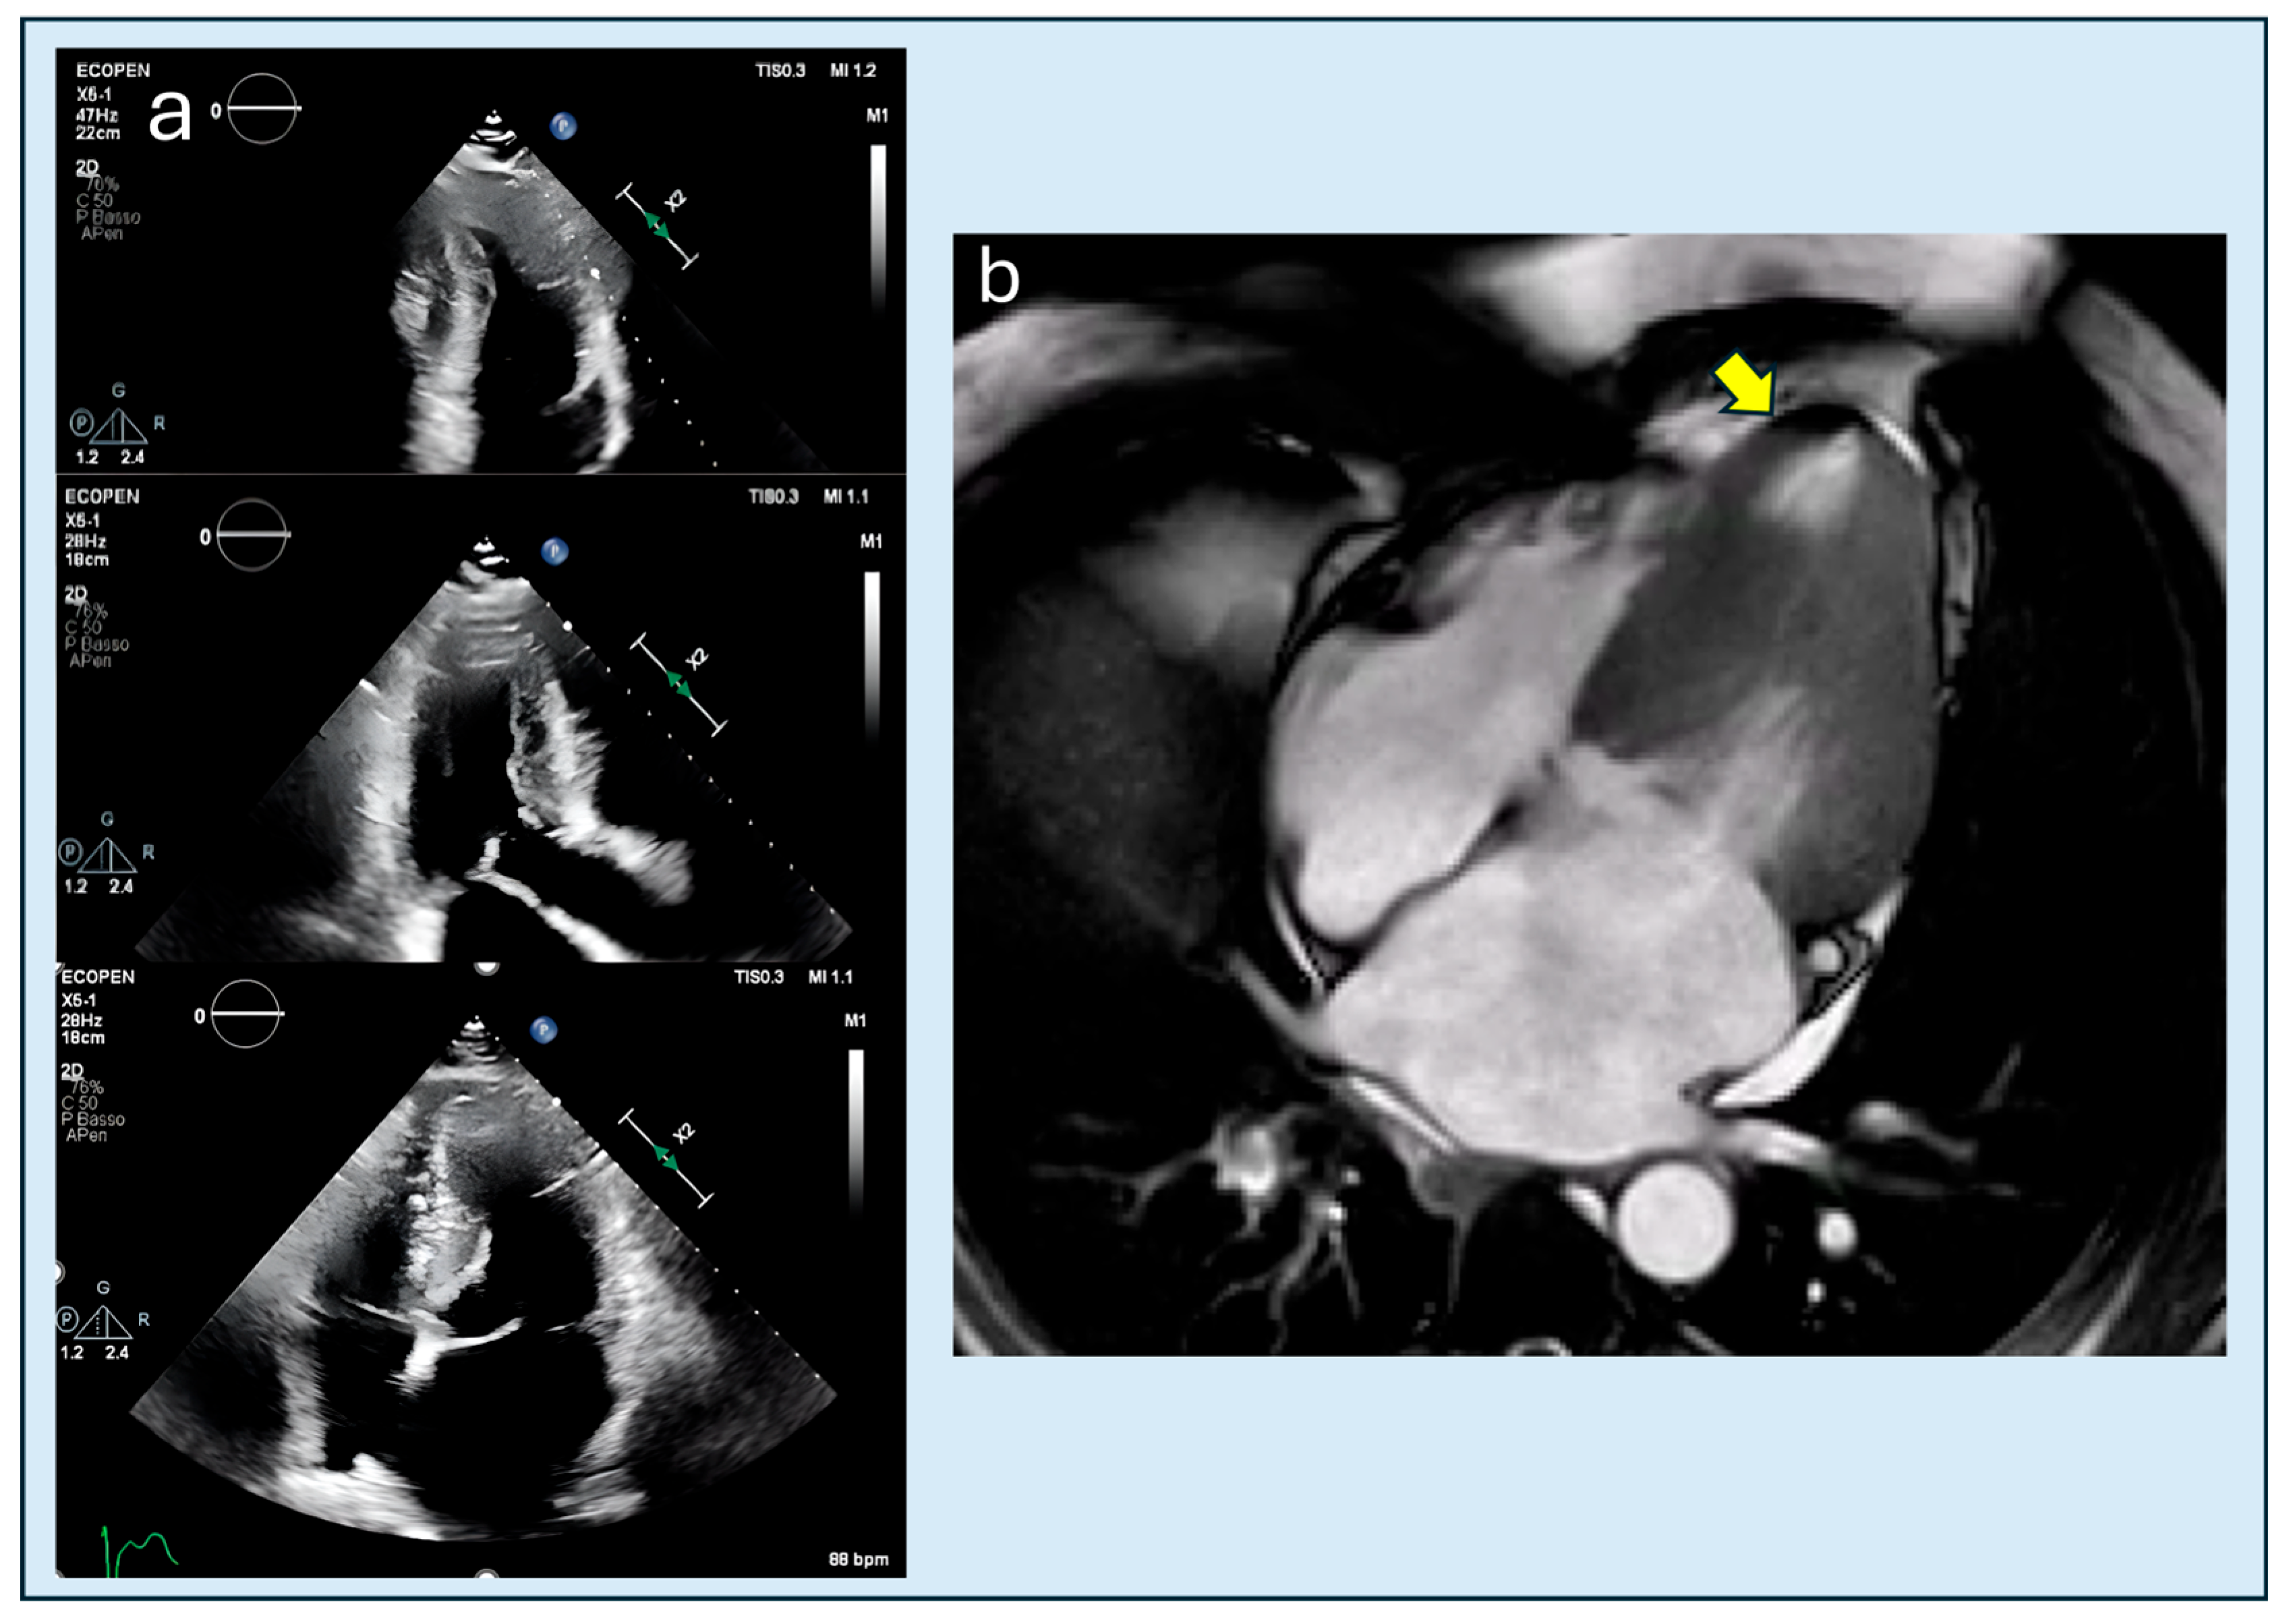

4.1. Obstruction

- Sherrid, M.V.; Bernard, S.; Tripathi, N.; Patel, Y.; Modi, V.; Axel, L.; Talebi, S.; Ghoshhajra, B.B.; Sanborn, D.Y.; Saric, M.; et al. Apical Aneurysms and Mid-Left Ventricular Obstruction in Hypertrophic Cardiomyopathy. JACC Cardiovasc. Imaging 2023, 16, 591–605. [Google Scholar] [CrossRef] [PubMed]

- Lee, D.Z.J.; Montazeri, M.; Bataiosu, R.; Hoss, S.; Adler, A.; Nguyen, E.T.; Rakowski, H.; Chan, R.H. Clinical Characteristics and Prognostic Importance of Left Ventricular Apical Aneurysms in Hypertrophic Cardiomyopathy. JACC Cardiovasc. Imaging 2022, 15, 1696–1711. [Google Scholar] [CrossRef] [PubMed]